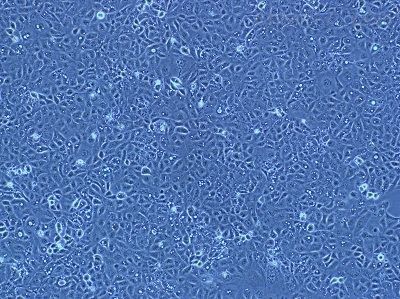

| 细胞名称 | NCI-H446 [H446]人小细胞肺癌细胞; |

| 背景资料 | 该细胞是1982年由Carney D和Gazdar AF等从一位小细胞肺癌患者的胸腔积液中建立的。细胞的原始形态并不具有小细胞肺癌特征。这个细胞株是小细胞肺癌的生化和形态学上的变种,表达神经元特有的烯醇酶和脑型肌酸激酶同工酶;左旋多巴脱羧酶、蚕素、抗利尿激素、催产素或胃泌激素释放肽未达到可检测水平。与正常细胞相比,该细胞c-myc DNA序列扩增约20倍,RNA增加15倍。初传代培养基用含有5%FBS的RPMI-1640,另外添加10 nM氢化可的松、0.005 mg/mL胰岛素、0.01 mg/mL转铁蛋白、10 nM 17-beta-雌二醇、30 nM 。 |

| 细胞形态 | 贴壁;上皮细胞样 |

| 细胞活力 | 95%(Viability by Trypan Blue Exclusion) |

| 培养条件 | RPMI-1640 +10% FBS;37℃,5% CO2 |

| 传代方法 | 建议1:2-1:3 两天换液一次 |